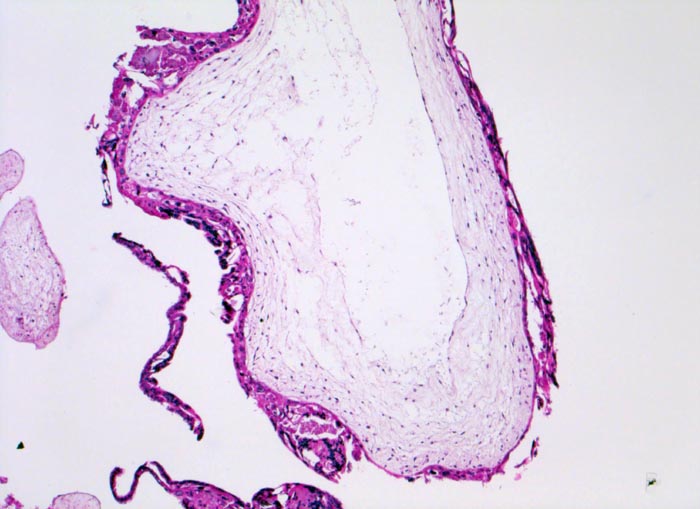

PathoPic ID 5125 - Blasenmole

Blasenmole

angeboren /genetisch/Missbildung

Abortmaterial

Paidopathologie

Blasig aufgetriebene Plazentarzotte mit zentraler pseudozystischer Hohlraumbildung (=

Zysterne) und zirkulär proliferiertem

Trophoblastepithel.

beta HCG Level von 150'000 mIU/mL. Uterus zu gross für das Gestationsalter von 10 Wochen. Arterielle Hypertonie.

Histologie

50